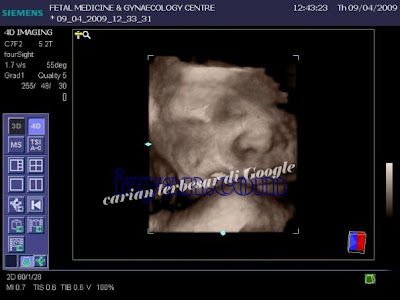

Entah betul entah tidak itu penulis belum lagi mendapat kepastian mutlak. Ada seorang peminat hiburan tanah air ni mendakwa imej komputer dibawah merupakan imej imbasan anak sulung kepada pasangan Malique Too Phat dan Melissa Maureen yang diambil di hospital.

Gambar X-ray anak Melissa dan Malique